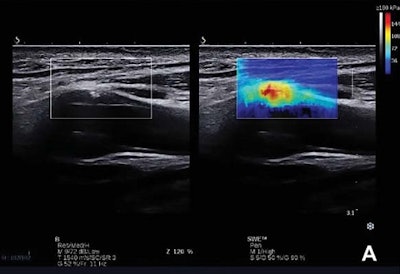

A shear-wave ultrasound elastography method can be used to evaluate the stability of carotid plaques, helping to identify those that are most vulnerable to rupturing and causing a stroke, according to a study published in the June issue of the Journal of Ultrasound in Medicine.

All patients received a clinical carotid ultrasound examination in conjunction with shear-wave elastography using an Aixplorer (SuperSonic Imagine) ultrasound scanner with a L10-2 MHz linear array transducer. Shear-wave elastography analysis was successfully carried out in 271 (92%) of the 295 plaques evaluated in the study, and the scanner's built-in Q-Box-Trace software tool was used to quantify the maximum, mean, and minimum Young's modulus values.

When confounding factors such as gender and smoking history were controlled, the researchers found a significant correlation between Gray-Weale plaque classification and mean Young's modulus (r = 50.728, p < 0.01). In addition, the mean Young's modulus of representative plaques in the symptomatic group was 81 kPa, compared with 115 kPa in the asymptomatic group. The difference was statistically significant (p < 0.01).

The researchers noted that the vulnerability of the whole plaque can be determined by calculating its Young's modulus measure on shear-wave elastography.

"The lower mean Young's modulus indicates a greater proportion of lipid cores, which could imply greater vulnerability than plaques with a higher fibrous content," they wrote.